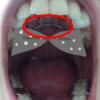

[돌출입 교정후기 8화] 하악과 상악 고무줄 교체

안녕하세요ㅎㅎ 저 왜 이렇게 자주 교정후기를 남기는 것 같죠?ㅎㅎ 확실히 월치료가 ...

[돌출입 교정후기 7화] 하악 스크류 및 상악과 하악 고무줄 교체

안녕하세요! 다들 잘 지내셨나요:)? 요새 일교차도 크고 건조해서, 감기 걸리기 쉽다던...

[돌출입 교정후기 6화] 상악 스크류 식립 및 하악 쉬어가기.

안녕하세요:-) 벌써 3월 돌출입교정 월치료를 다녀왔습니다!ㅎㅎ 그동안 바이트블럭에...